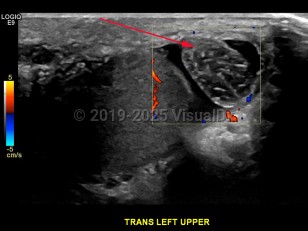

Testicular torsion

Physical examination will show a raised testicle and absent cremasteric reflex. The testicle is often swollen and tender with an abnormal lie. Scrotal edema and tenderness may also be present, although the condition may be painless in approximately 10% of affected patients. The scrotum may also appear reddened or darkened on the affected side.

Best Tests